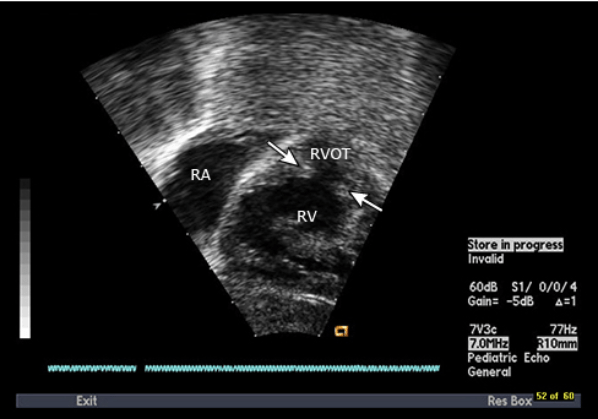

Lastly, we can use bedside ECHO to try and evaluate some of the features of ToF.

Ventricular septal defect appearing as a gap between the two septums on parasternal long axis view.

Pulmonary outflow tract obstruction seen as discontinuation of blood flow from the right ventricle

RV hypertrophy seen as enlargement of the RV when compared to the LV.

In our patient, she had an upturned heart with boot like shape, suggestive of ToF but did not have any of the other signs like lack of peripheral vascularity or hyperinflated lungs. We did do a bedside ultrasound and thought we witnessed some RV hypertrophy but were not able to find other parts of the heart to try and compare them to the above images to further evaluate ourselves. Since the patient was having intermittent episodes of hypoxia given her relatively normal chest x-ray, a decision was made to transfer to a tertiary facility for further evaluation.